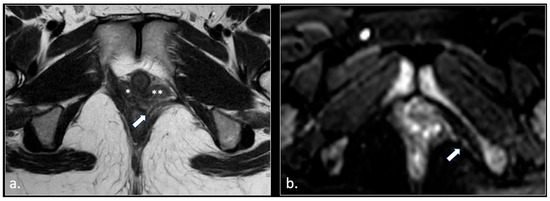

MRI in Chronic Pudendal Neuralgia: Diagnostic Criteria and Associated Pathologies

by Michele Gaeta, Sofia Turturici, Karol Galletta, Carmelo Geremia, Attilio Tuscano, Aurelio Gaeta, Marco Cavallaro, Salvatore Silipigni and Francesca Granata

Background/Objectives: Chronic pudendal neuralgia is a relatively rare condition in the general population, with an incidence of 1%. Although diagnosis of pudendal neuralgia is mainly clinical, Magnetic Resonance Imaging (MRI) is commonly performed to obtain further information. However, clear criteria and guidelines for MRI diagnosis and the clinical–radiological correlation are still not definite. Methods: We reviewed 81 patients with chronic pudendal neuralgia, studied by an MRI designed protocol for a pelvis and pelvic floor examination. A key element of the protocol was the use of a diffusion-weighted imaging (DWI) technique with echo planar imaging (EPI) sequence (b-values of 0, 100, and 600) for the neurographic evaluation of the nerve. Results: MRI examination revealed DWI abnormalities in 42/81 patients. Pudendal nerve abnormalities were unilateral in 33/42 patients and bilateral in 9/42. Moreover, in 23/42 patients, pathologies related to a high probability of neuropathy have been identified. Conclusions: This study highlights the role of pelvic MRI as a valuable imaging modality in the evaluation of patients with chronic pudendal neuralgia. In the study protocol we propose, an essential role is played by the DWI technique, which improves the visual definition of the pudendal nerve and related anatomical structures. By focusing on anatomical visualization and structured image interpretation, our work provides a practical imaging-oriented contribution to a field in which standardized MRI evaluation is still lacking. Full article